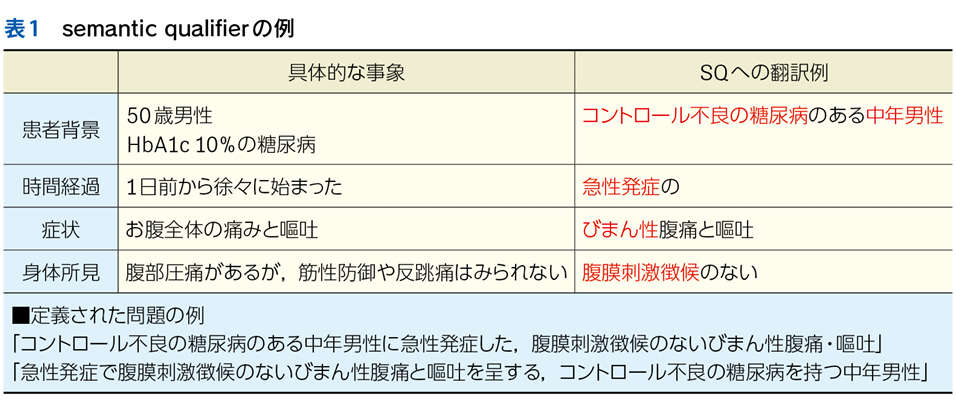

▶ semanticは直訳すれば「意味の」となるが,semantic qualifierを診断推論の文脈で訳すなら,「意味を限定する修飾語句」とでもなるだろう。先述のように,フレーミングに用いる問題を定義するにあたっては,個別具体的な情報は捨象され,抽象化・一般化された概念となっている必要がある。ゆえにSQも抽象的・一般的な医学用語に「翻訳」して表現する(表1)。